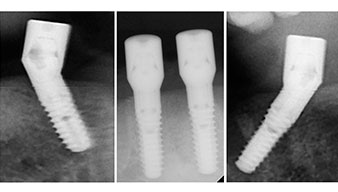

A three-dimensional cone beam computed tomography scan (CBCT, Planmeca) was performed to aid planning and minimize risks. This revealed that the quality and quantity of the available bone were sufficient for the surgery and immediate restoration using the Fast & Fixed method. Following the protocol for this concept, the implants are inserted at 35, 32, 42 and 45. Angling the distal implants by up to 45° shifts the emergence profile to posterior and generates a larger support polygon (Fig. 3).

Fast & Fixed method

Fig. 3